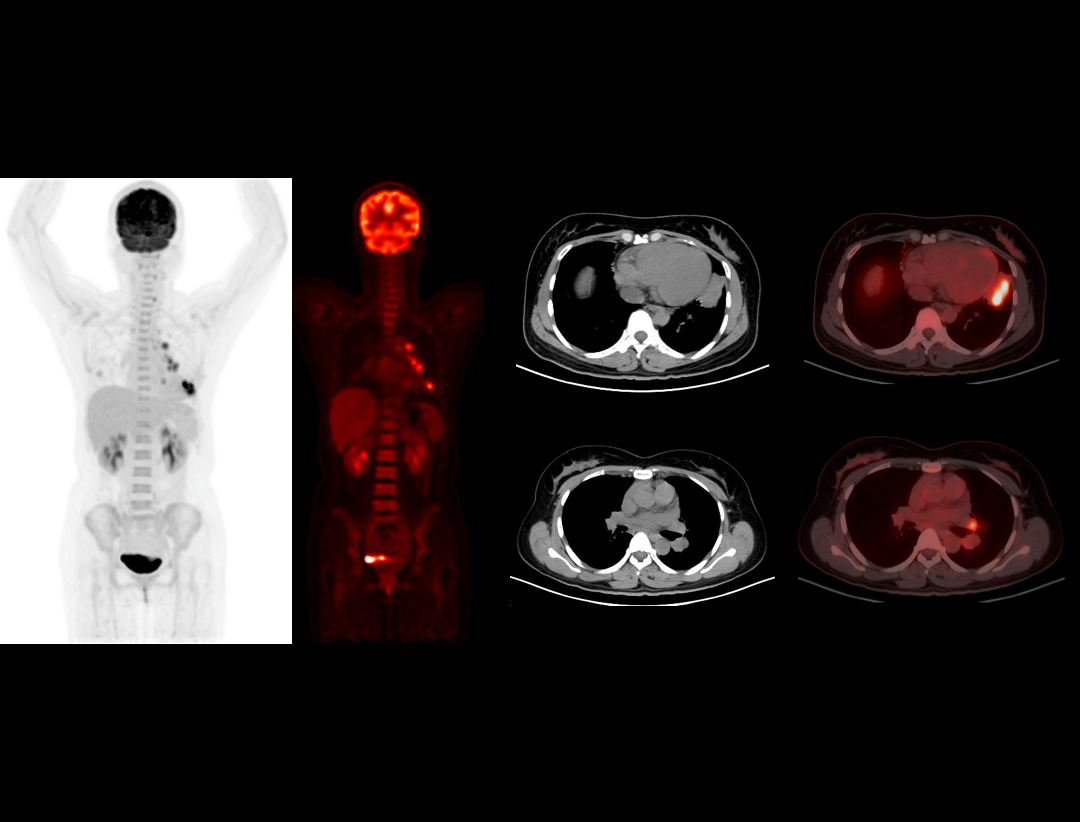

600 x 600

超大矩阵,高精度超清重建